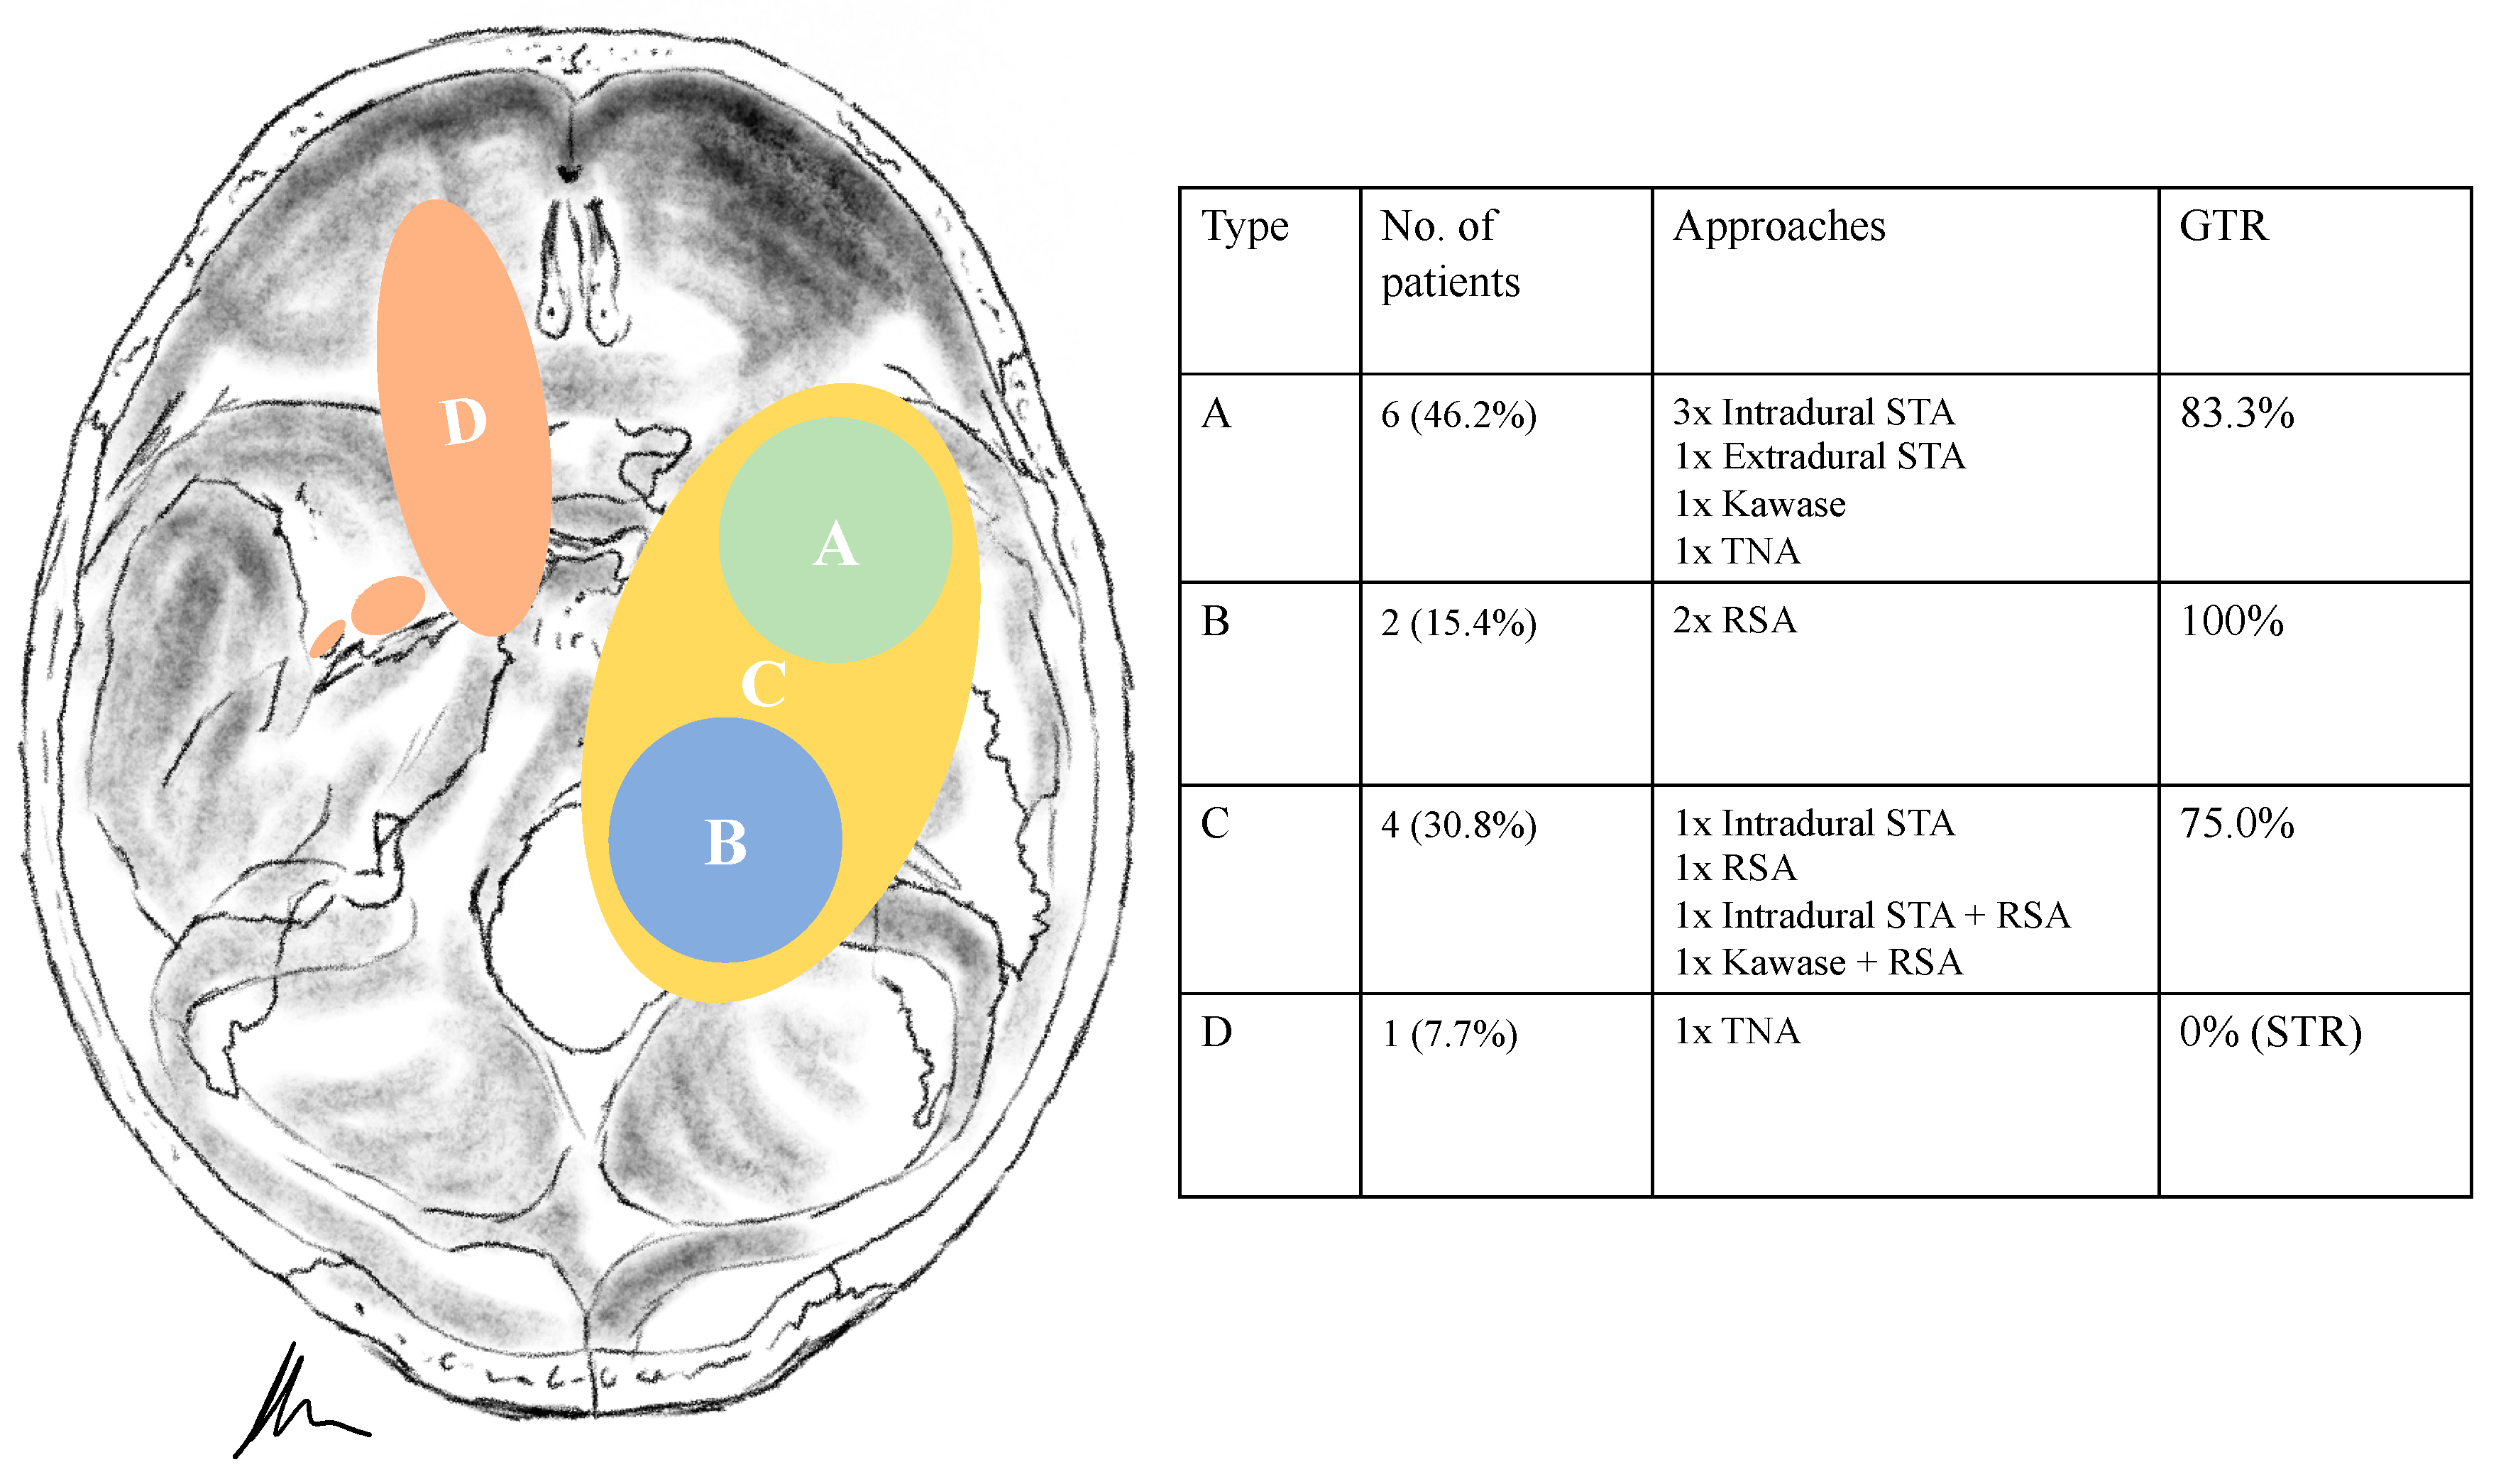

Figure 6. A 53-year-old female patient presented with vomiting, slight ataxia, facial pain and trigeminal hypesthesia (V1,V2) for three months. (A) Preoperative axial and (B) coronal T1-weighted gadolinium-enhanced MRI, showing a space-occupying cystic trigeminal schwannoma invading the cerebellopontine angle (Samii Type B). (C) Postoperative axial and (D) coronal MRI control, indicating complete resection via a retrosigmoid approach. Postoperatively, new temporary slight hypoacusis and facial neve palsy (House and Brackmann Grade III) occurred.